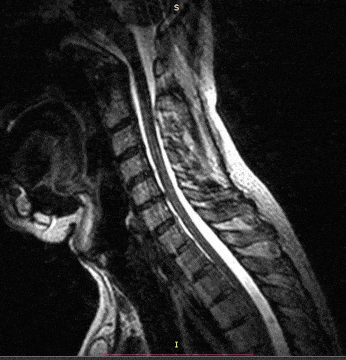

This doesn’t just happen from a traumatic injury however. As we get older, our bones begin to weaken, cartilage wears down, and you can be more susceptible to this. For that reason, central cord syndrome is more common in people over the age of 50 because they are at higher risk for cervical spondylosis. Spondylosis is degenerative changes in the spine such as bone spurs and degenerating intervertebral discs between the vertebrae, so cervical spondylosis is degeneration in the cervical area of the spine. However there is a caveat, this happens at a higher rate in older people. Central cord syndrome can and does happen in younger individuals as well. Just a reminder, the spinal cord moves quite a bit as you move around and below is an animated gif showing spinal cord movement from neck flexion and extension.

Look close to the brainstem and you can clearly see the cord move as the neck moves.